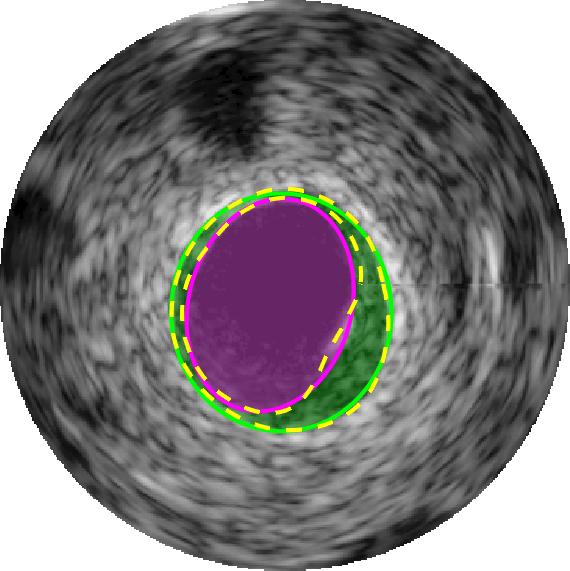

Qualitative evaluations are illustrated in Figure 4 and show the successful segmentation results of the proposed EREL selection strategy for 20 IVUS frames. The lumen areas are highlighted by the magenta colour while the media regions are green. Also, the manually annotated contours for both lumen and media are drawn as yellow dashed lines. As we can see, the chosen frames contain a variety of lumen and media morphologies.